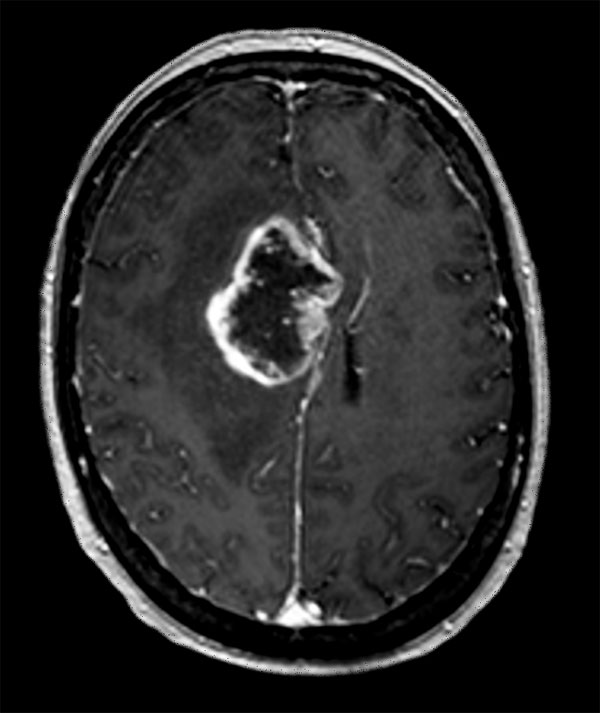

Advanced Neuro imaging - pCASL

Clinique Saint Joseph Imagerie Medicale, Liege, Belgium